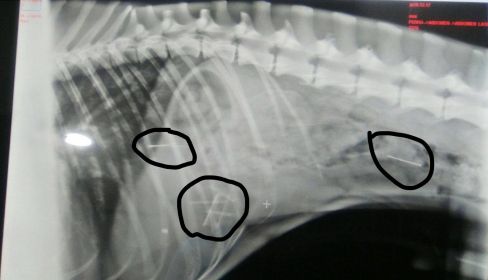

Desde entonces comenzó a alertar a sus conocidos. Pero al día siguiente, Flaco, el perro de Emi, comenzó a encontrarse mal. Ante la actitud del animal, y sabiendo que ella lo pasea "por esa zona", no dudó en llevarlo a un especialista. Efectivamente, tenía ocho clavos entre el intestino y el estómago. A pesar de ello, goza de una salud "aparentemente normal", pero solo ha logrado expulsar uno desde entonces y continúa con siete en su interior. Por ello, Ismael pide información con el objetivo de encontrar pistas que localicen al autor o autores de tan macabro plan, desde una visita al veterinario a un informe o una foto, "cualquier ayuda es buena", sentencia.

Jerónimo García, veterinario de la clínica Nueva Tavira que ha atendido al perro de Emi, advierte que "la vida de Flaco lleva corriendo peligro desde entonces, los clavos son objetos muy peligrosos porque, además de pinchar mucho, tiene todavía siete y son muy difíciles de localizar quirúrgicamente". A pesar de estar en sus días de vacaciones, no desconecta en ningún momento porque "es un caso muy delicado y que no te esperas". De hecho, no tiene dudas al afirmar que en este tipo de situaciones "si los dueños no están encima del animal se muere".